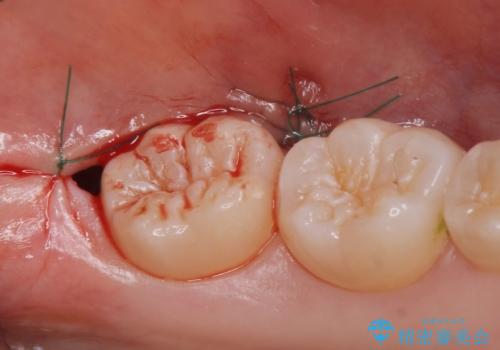

- 左上下親知らず抜きたいとの事で来院。

レントゲン、CTを撮影し安全を考慮して抜歯術を行いました。

抜歯後、1週間後に抜糸を行う必要があります。